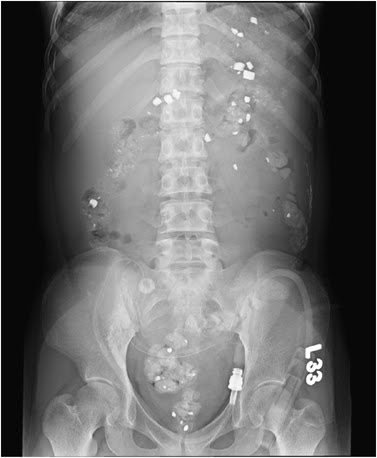

The picture above comes from a case report in KI where a PD patient presented with hypertension and edema. She was normally compliant and a plain film of her abdomen was performed to make sure that her catheter was properly sited. Densely radiopaque material was found to be present throughout her colon. There was no history of recent contrast studies and she was asymptomatic. What could cause this radiographic appeareance?

The answer to this mystery lay in her medications. She had been started on the phosphate binder lanthanum carbonate 3 months previously. Lanthanum is a rare earth metal which lies next to barium on the periodic table and has a high affinity for phosphate. It has little systemic absorption and low solubility and remains largely in the intestine after ingestion. It is a high density material with a density between that of bone and metal. The CT above shows lanthanum tablets in the stomach which have a higher density (3000HU) than the radiocontrast in the aorta (450HU). This accumulation appears to cause no ill effects and disappears once the drug is stopped or with the use of laxatives. The main issue is that it may interfere with the interpretation of xrays and radiologists should be informed that a patient is on this drug prior to abdominal imaging in order to prevent confusion.